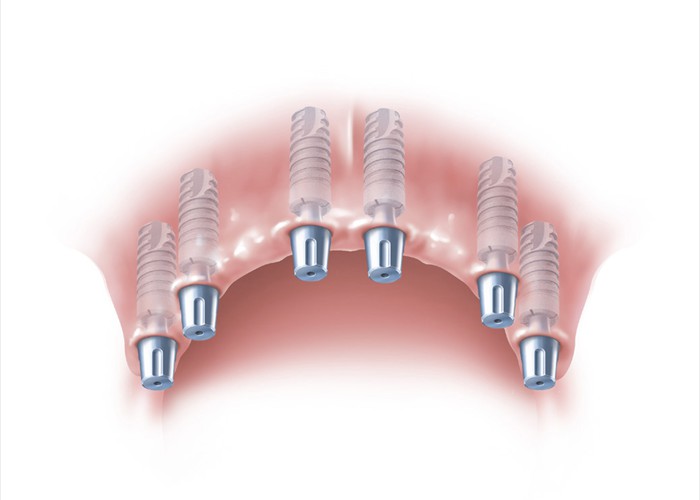

Einbringen von 6 Implantaten für eine festsitzende Versorgung

Einbringen von 6 Implantaten für eine festsitzende Versorgung

Das Einsetzen des fertigen Zahnersatzes

Das Einsetzen des fertigen Zahnersatzes